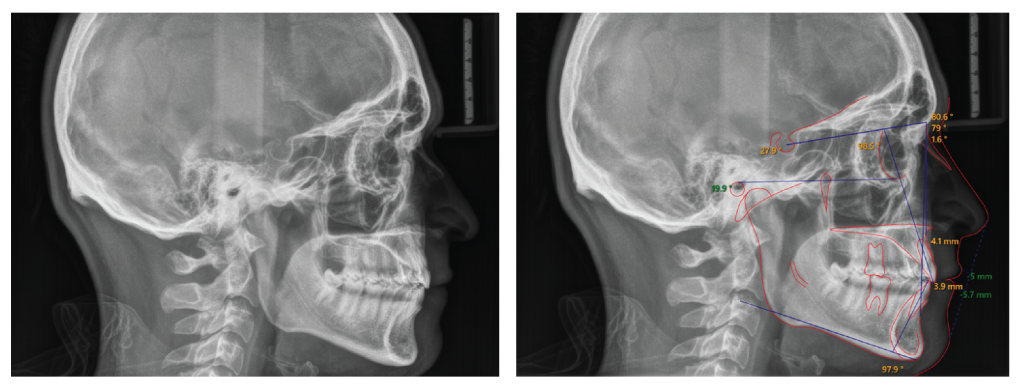

The panoramic radiograph (Figure 3) revealed a complete dentition except for the maxillary third molars, which had been previously extracted. The roots of all teeth were fully developed, but there were signs of blunting on the maxillary left central and a fracture at the tip of the apex on the maxillary lateral incisor. Remodeling of the condyles was also observed. Lateral cephalometric analysis (Figure 4 and Table I) revealed a skeletal Class I relation (ANB= 2°) with a hypo-divergent mandible (FMA = 19.5°). The inclinations of the maxillary and mandibular incisors were within normal limits, with U1°- SN measuring 101.2° and IMPA measuring 99.3°, respectively). Soft tissue analysis indicated that the distances from the upper and lower lips to the E-line were deficient, measuring -4.9 mm and -5.2 mm, respectively.

Figure 4: Pre-treatment lateral cephalometric radiograph and analysis. Pre-treatment lateral cephalometric radiograph shows a skeletal Class I jaw relation (ANB is 2°), hypo-divergent mandible (FMA is 19.5°), and upper and lower incisor inclination within normal limits. Soft tissue analysis indicates that the distances from the maxillary and mandibular lips to the E-line were increased, suggesting lip retrusion.